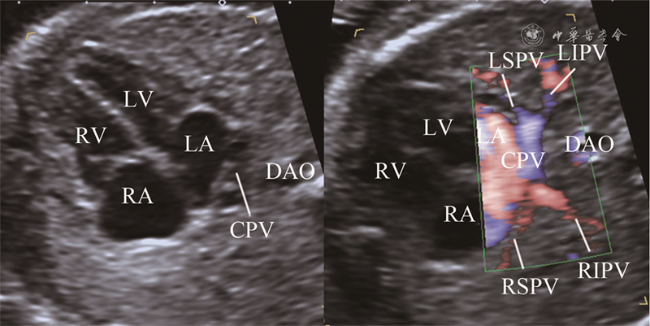

图2 胎儿心上型完全型肺静脉异位引流超声图像。右图胸部横切面彩色血流显示左上肺静脉远端分支分布于左侧前部1/2肺野,左下肺静脉远端分支分布于左侧后部1/2肺野,右上肺静脉远端分支分布于右侧前部1/2肺野,右下肺静脉远端分支分布于右侧后部1/2肺野(对应动态图2),4条肺静脉近心端均未回流入左心房,呈现左心房后方汇聚征,肺静脉分支间距减小;左图为二维超声对比图像

动态图2 胎儿心上型完全型肺静脉异位引流超声动态图像

追踪36例TAPVD胎儿肺组织4大区域回流显示4条肺静脉均未汇入左心房,34例肺静脉近心端呈现左心房后方汇聚征(图2动态图2),包括心上型25例,心内型7例,心下型2例。心上型TAPVD胎儿,其中20例4条肺静脉于左心房后方汇聚成肺总静脉腔,然后向头侧走行,最终汇入上腔静脉;3例胎儿显示3条肺静脉引流3大区域,于左心房后方汇聚成肺总静脉腔,肺总静脉腔向头侧走行过程中收集剩余区域肺静脉1条共同入上腔静脉。心内型TAPVD胎儿7例,其中6例4条肺静脉于左心房后下部汇聚成肺总静脉腔回流入冠状静脉窦,1例4条肺静脉于左心房后方汇聚成肺总静脉腔,直接回流入右心房。心下型TAPVD胎儿2例,4条肺静脉均于左心房后方汇聚成肺总静脉腔,然后向足侧走行汇入门静脉窦。混合型TAPVD 2例,1例左侧上肺及下肺静脉汇合后向头侧走行汇入上腔静脉,右侧上肺及下肺静脉汇合后向足侧走行入下腔静脉;1例左侧上肺及下肺静脉汇合后向头侧走行入上腔静脉,右侧上肺及下肺静脉汇合后直接回流入右心房。

二、区域血流追踪法与APVD胎儿超声诊断

应用区域血流定位好肺静脉分支后,继续追踪其是否回流入左心房,用于鉴别正常与APVD胎儿。本研究中36例TAPVD胎儿呈现左心房后方汇聚征,而正常胎儿汇入左心房的声像图表现呈螃蟹征,如同4条“腿”插入左心房壁。二者区别在于正常胎儿4条肺静脉插入左心房壁之间,且分支间距较大,而TAPVD胎儿肺静脉向左心房后方共同肺静脉腔汇聚,分支间距较小,在彩色血流辨别不清时,需结合二维超声对比观察。本研究中3例TAPVD胎儿3条肺静脉汇入共同肺静脉腔,通过区域血流追踪发现剩余1条肺静脉在共同肺静脉腔移行为垂直静脉的过程中汇入,这也使得这3例胎儿最终诊断为TAPVD。对共同肺静脉腔的血流进一步追踪,可显示肺静脉向上、向下、向冠状静脉窦或直接向右心房回流,从而对TAPVD的分型做进一步的判断。